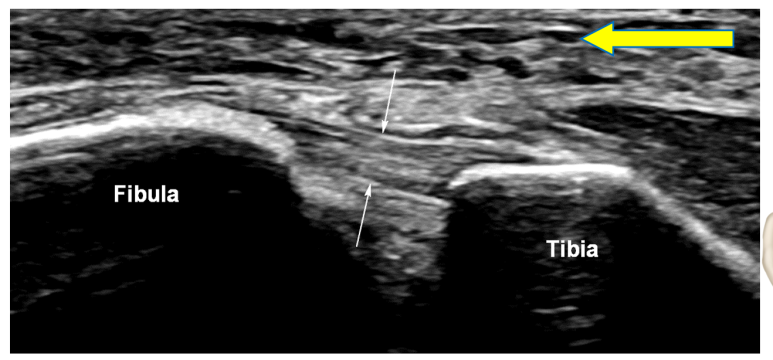

영상에서

전하경비인대는 이렇게 보입니다.

인대 내부 섬유 패턴이

하얗게 잘 보이면서 인대 표면이

경골과 비골을 연결하는 선을넘어가지 않습니다. 그런데 위 환자분은

없어지면서 까맣게 보이고요. 인대가 늘어나

많이 부어있는 상태였습니다.